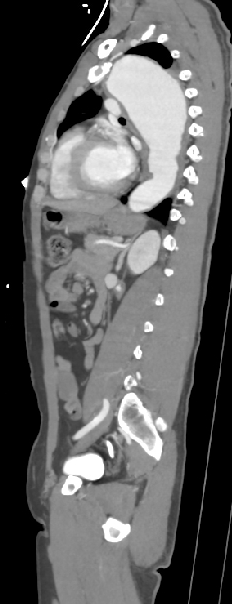

55 male chronic HTN not on optimum medical Treatment, after a fight with his colleagues developed Right Side Hemiparesis.  Diagnosis ?  What further i